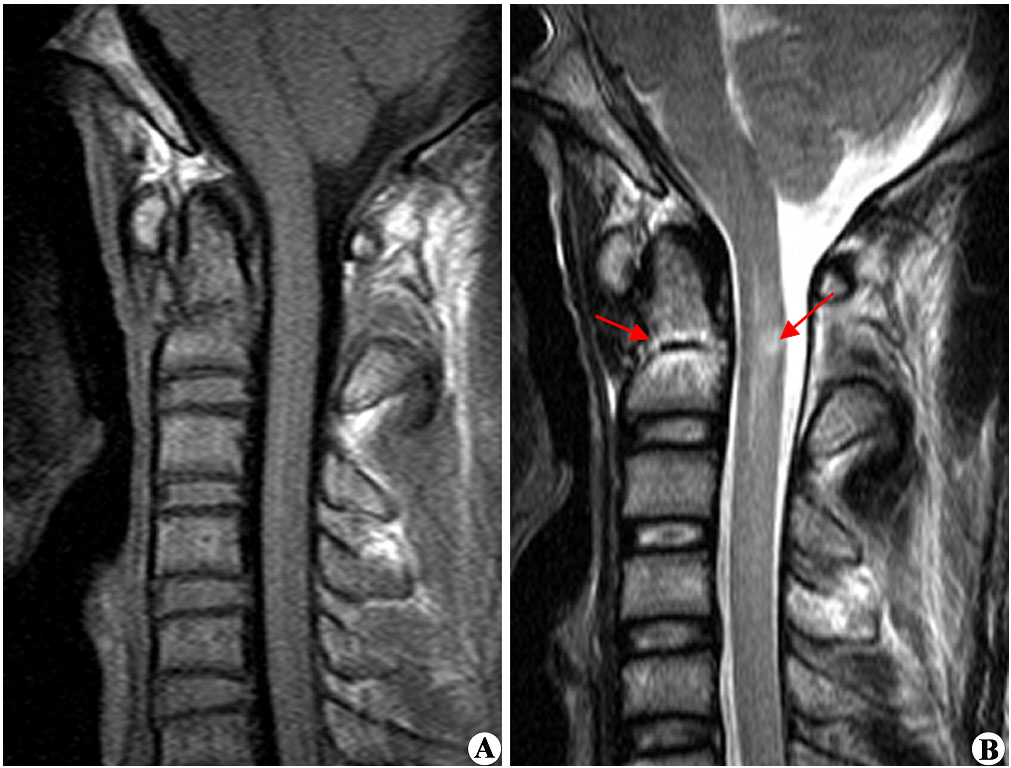

1、再次手术切除:如患者自身条件符合再次手术切除的标准,一般手术可以处理复发的肿瘤。针对脊髓肿瘤的手术切除,显微外科手术是主要的方法,近年来显微外科器械、手术技术的进步,成功率提高,致残率下降。再次手术难度和风险均是增大了很多,选择手术的医生要谨慎,否则不仅不能切干净,而且术中还可能导致危险。目前,INC国际神经外科医生集团旗下国际神经外科顾问团成员巴特朗菲教授、Sebastien Froelich教授、James T. Rutka教授作为国际脑瘤手术教授,他们不仅能对脊髓肿瘤实施高切除率手术,而且术后神经功能无明显损伤,让患者的生活质量也较术前有了很大的提高。

2、放射治疗。对于无法再次手术切除、或者手术仍然有残余肿瘤的脊髓肿瘤患者,放疗是临床常用的策略。脊髓肿瘤有些位置手术注定难以切除干净,放疗可用于消除手术后残留的肿瘤残余。不能手术的肿瘤或手术风险太大的肿瘤,这时候可以通过放射治疗加以辅助,来帮助控制、减少受损细胞,让治疗效果更好。